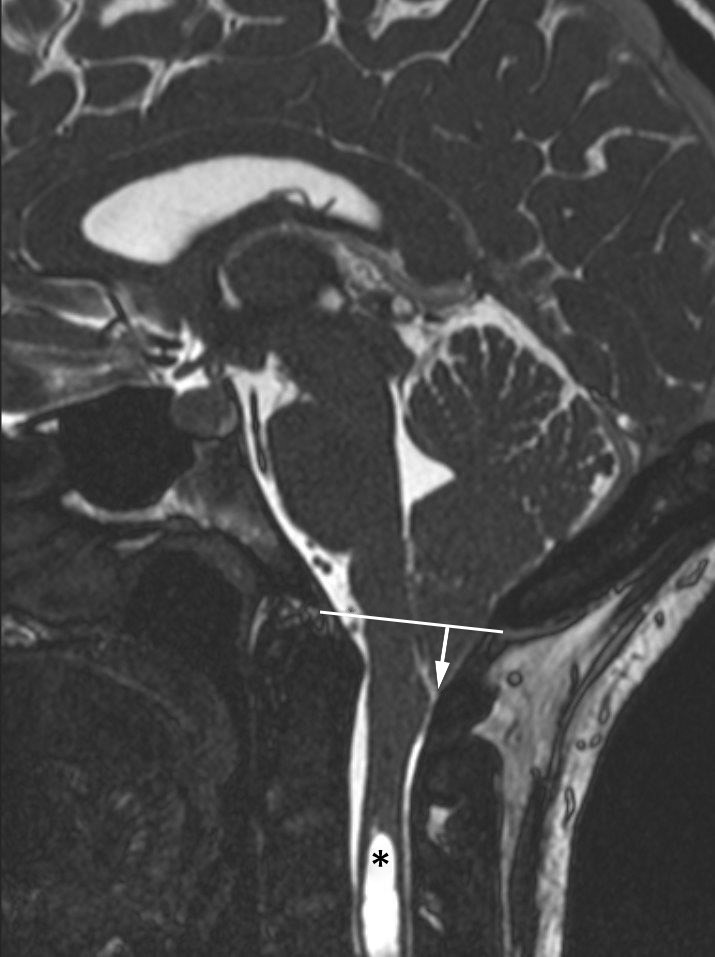

Chiari-malformasjon type 1 diagnostiseres ofte tilfeldig hos pasienter henvist til MR av ulike årsaker. Påvisningens betydning for symptomer som kan relateres til tilstanden, bør avklares med nevrolog. Som MR-kriterium for diagnosen skal det påvises ektopi av lillehjernetonsiller > 5 mm under nivå med foramen magnum, definert av en linje mellom basion og opisthion (figur 1).

Ryggmargstjoring er en kjent mekanisme ved Chiari-malformasjon type 2, der denne er til stede grunnet medfødt ryggmargsbrokk, typisk lumbosakralt. Under lengdevekst av ryggraden strekkes den tjorede ryggmargen, noe som i sin tur strekker nervestrukturer i bakre skallegrop ned gjennom foramen magnum. Når denne mekanismen knyttes til Chiari-malformasjon type 1, antas det å foreligge en okkult, moderat variasjon av spinal dysrafisme (10). Dette er imidlertid meget sjelden tilfelle. Funn som eventuelt indikerer ryggmargstjoring, for eksempel et fibrolipom i filum terminale (figur 2), kan langt på vei utelukkes ved MR av columna. Teorier om ryggmargstjoring som en eksklusiv bakenforliggende årsak til type 1-malformasjon er lite berettiget, og også denne mekanismen er sannsynligvis aktuell kun hos liten andel av pasientene (10).

Norske medier har nylig omtalt kirurgisk behandling av Chiari-malformasjon type 1 på en klinikk i utlandet, der flere norske pasienter har blitt behandlet. Etter det vi erfarer, består denne behandlingen av kirurgisk klipping av filum terminale, en tynn streng av fibrøst vev longitudinelt forløpende mellom conus medullaris og nedre del av duralsekken. Denne strukturen har ingen fysiologisk funksjon, men kan i visse tilfeller ligge såpass festet kaudalt i spinalkanalen at det forårsaker stramming av ryggmargen. Denne tjoringen er en vanlig problemstilling hos barn med medfødt ryggmargsbrokk og Chiari-malformasjon type 2 og/eller intraspinale lumbosakrale lipomer, eventuelt assosiert med et smalt fibrolipom i filum terminale (fatty filum) figur 2). I barnenevrokirurgisk praksis er klipping av filum terminale et relativt vanlig inngrep, men det er meget sjelden indisert hos voksne pasienter med Chiari-malformasjon type 1, unntatt hos en liten undergruppe med tjoring (adult tethered cord syndrome) ((10).